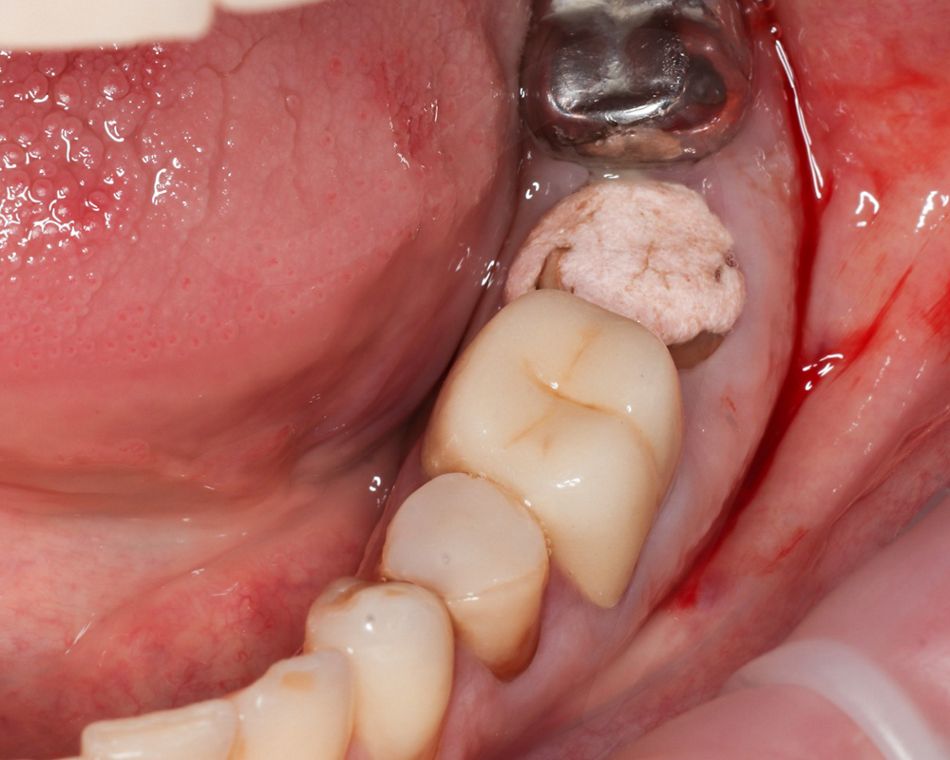

Поскольку сохранение альвеолярной кости имеет решающее значение для успеха немедленной имплантации, перед извлечением корней между ними подготовили фрезами ложа под имплантаты, чтобы избежать деформации кости на пути бурения, а затем с особой осторожностью удалили корни (Илл. 2).

Стенки лунки сохранили нетронутыми и тщательно освободили от грануляционной ткани, промыли стерильным раствором.

Иллюстрация 2